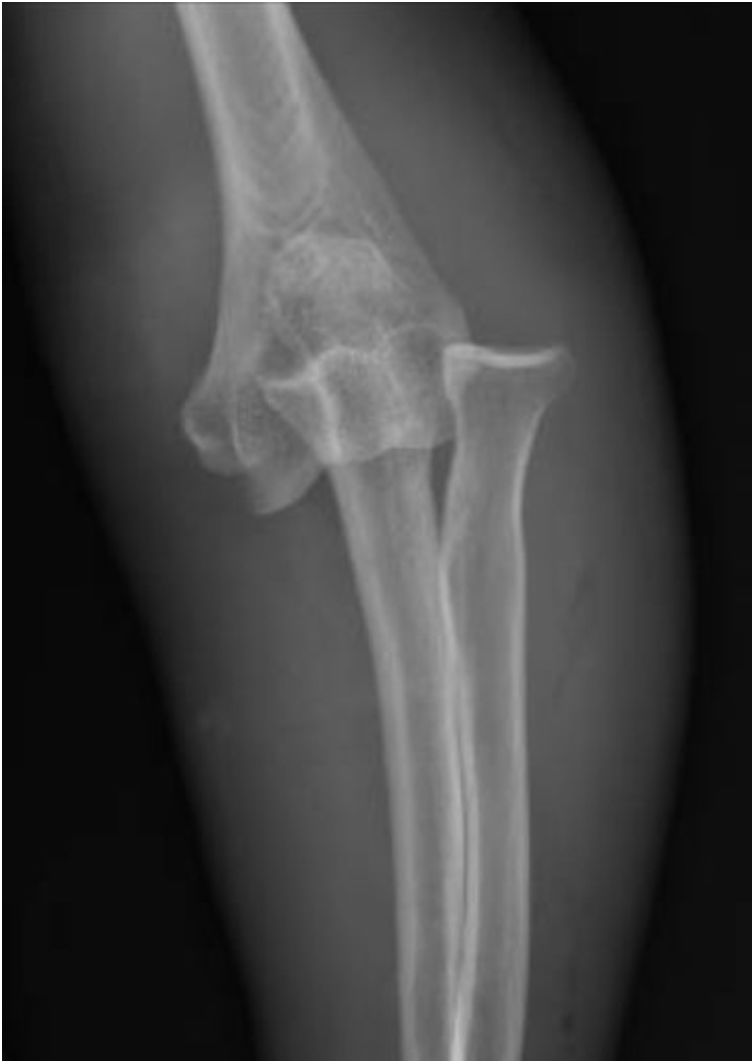

Luxación de codo AP: Ciertos accidentes pueden ocasionarnos que el codo se “safe” esto consiste en la dislocación o luxación del húmero distal del olécranon y de la cúpula radial. En esta radiografía vemos como se observa desde frente la lesión, y en la siguiente →

Luxación de codo LATERAL: observamos cómo se diagnóstica la luxación de codo en una radiografía desde perfil.